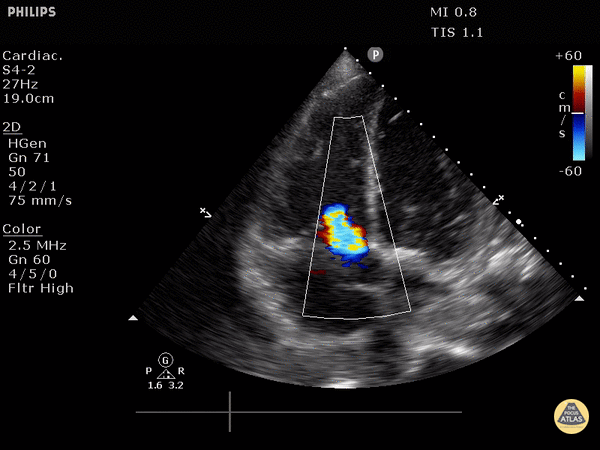

Moderate to severe tricuspid regurgitation demonstrated on apical 4 chamber view. Justin Bowra MBBS, FACEM, CCPU Emergency Physician, RNSH et al. (Dr. Kaynama)